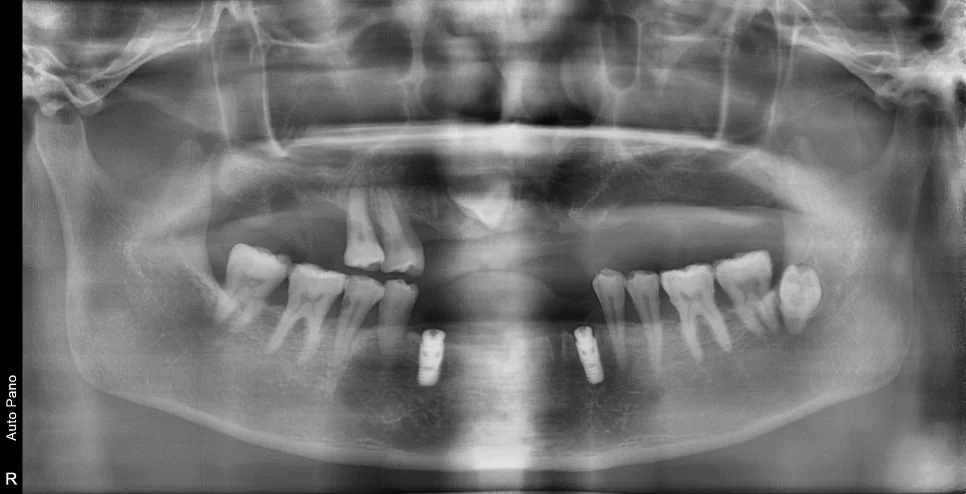

수술 전후 파노라마 비교

CBCT 단면 – 각 임플란트 개별 검증

CT 상에서 하얀색인 임플란트가 1. 온전히 뼈 안에 잠기게(1~2mm 깊게) 그리고 2. 가급적이면 입천장 쪽으로 식립되었다면 잘 심긴 임플란트입니다. (입술 쪽 뼈는 쉽게 흡수됩니다ㅜ)